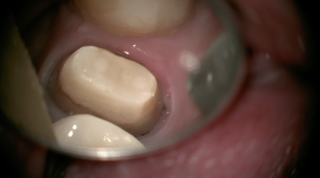

上の歯にファイバーコアを入れた歯です。